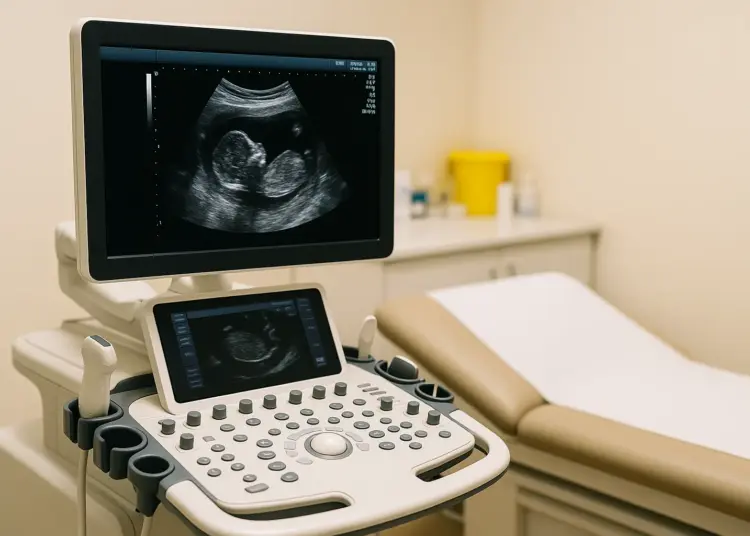

Concerns have been raised by leading radiographers regarding the presence of “unsafe” high street clinics offering ultrasound scans for expectant parents, amid alarming reports of serious misdiagnoses and overlooked medical emergencies. The Society of Radiographers (SoR) has indicated that an increasing number of these private establishments are providing pregnancy scans, often staffed by personnel who lack the necessary training and qualifications.

According to the SoR, the lack of regulation allows anyone with access to an ultrasound machine to label themselves as a sonographer, a significant deviation from the standards required of other healthcare professionals who must undergo proper training before practicing. This unregulated environment poses considerable risks to both mothers and their babies, potentially leading to life-threatening situations.

The SoR is advocating for the establishment of a “protected” title for sonographers. This measure would ensure that only individuals who are properly qualified and registered with a recognised regulatory body can designate themselves as sonographers. Katie Thompson, president of the SoR and an experienced hospital sonographer, emphasised the public’s assumption that individuals performing scans are appropriately qualified. “When people go for a scan or any kind of diagnostic test, they assume that the person they’re going to see is qualified to do it. They don’t realise that anybody can buy a machine and call themselves a sonographer,” she explained. With a formal registration, patients would have recourse to a regulatory body should any issues arise.